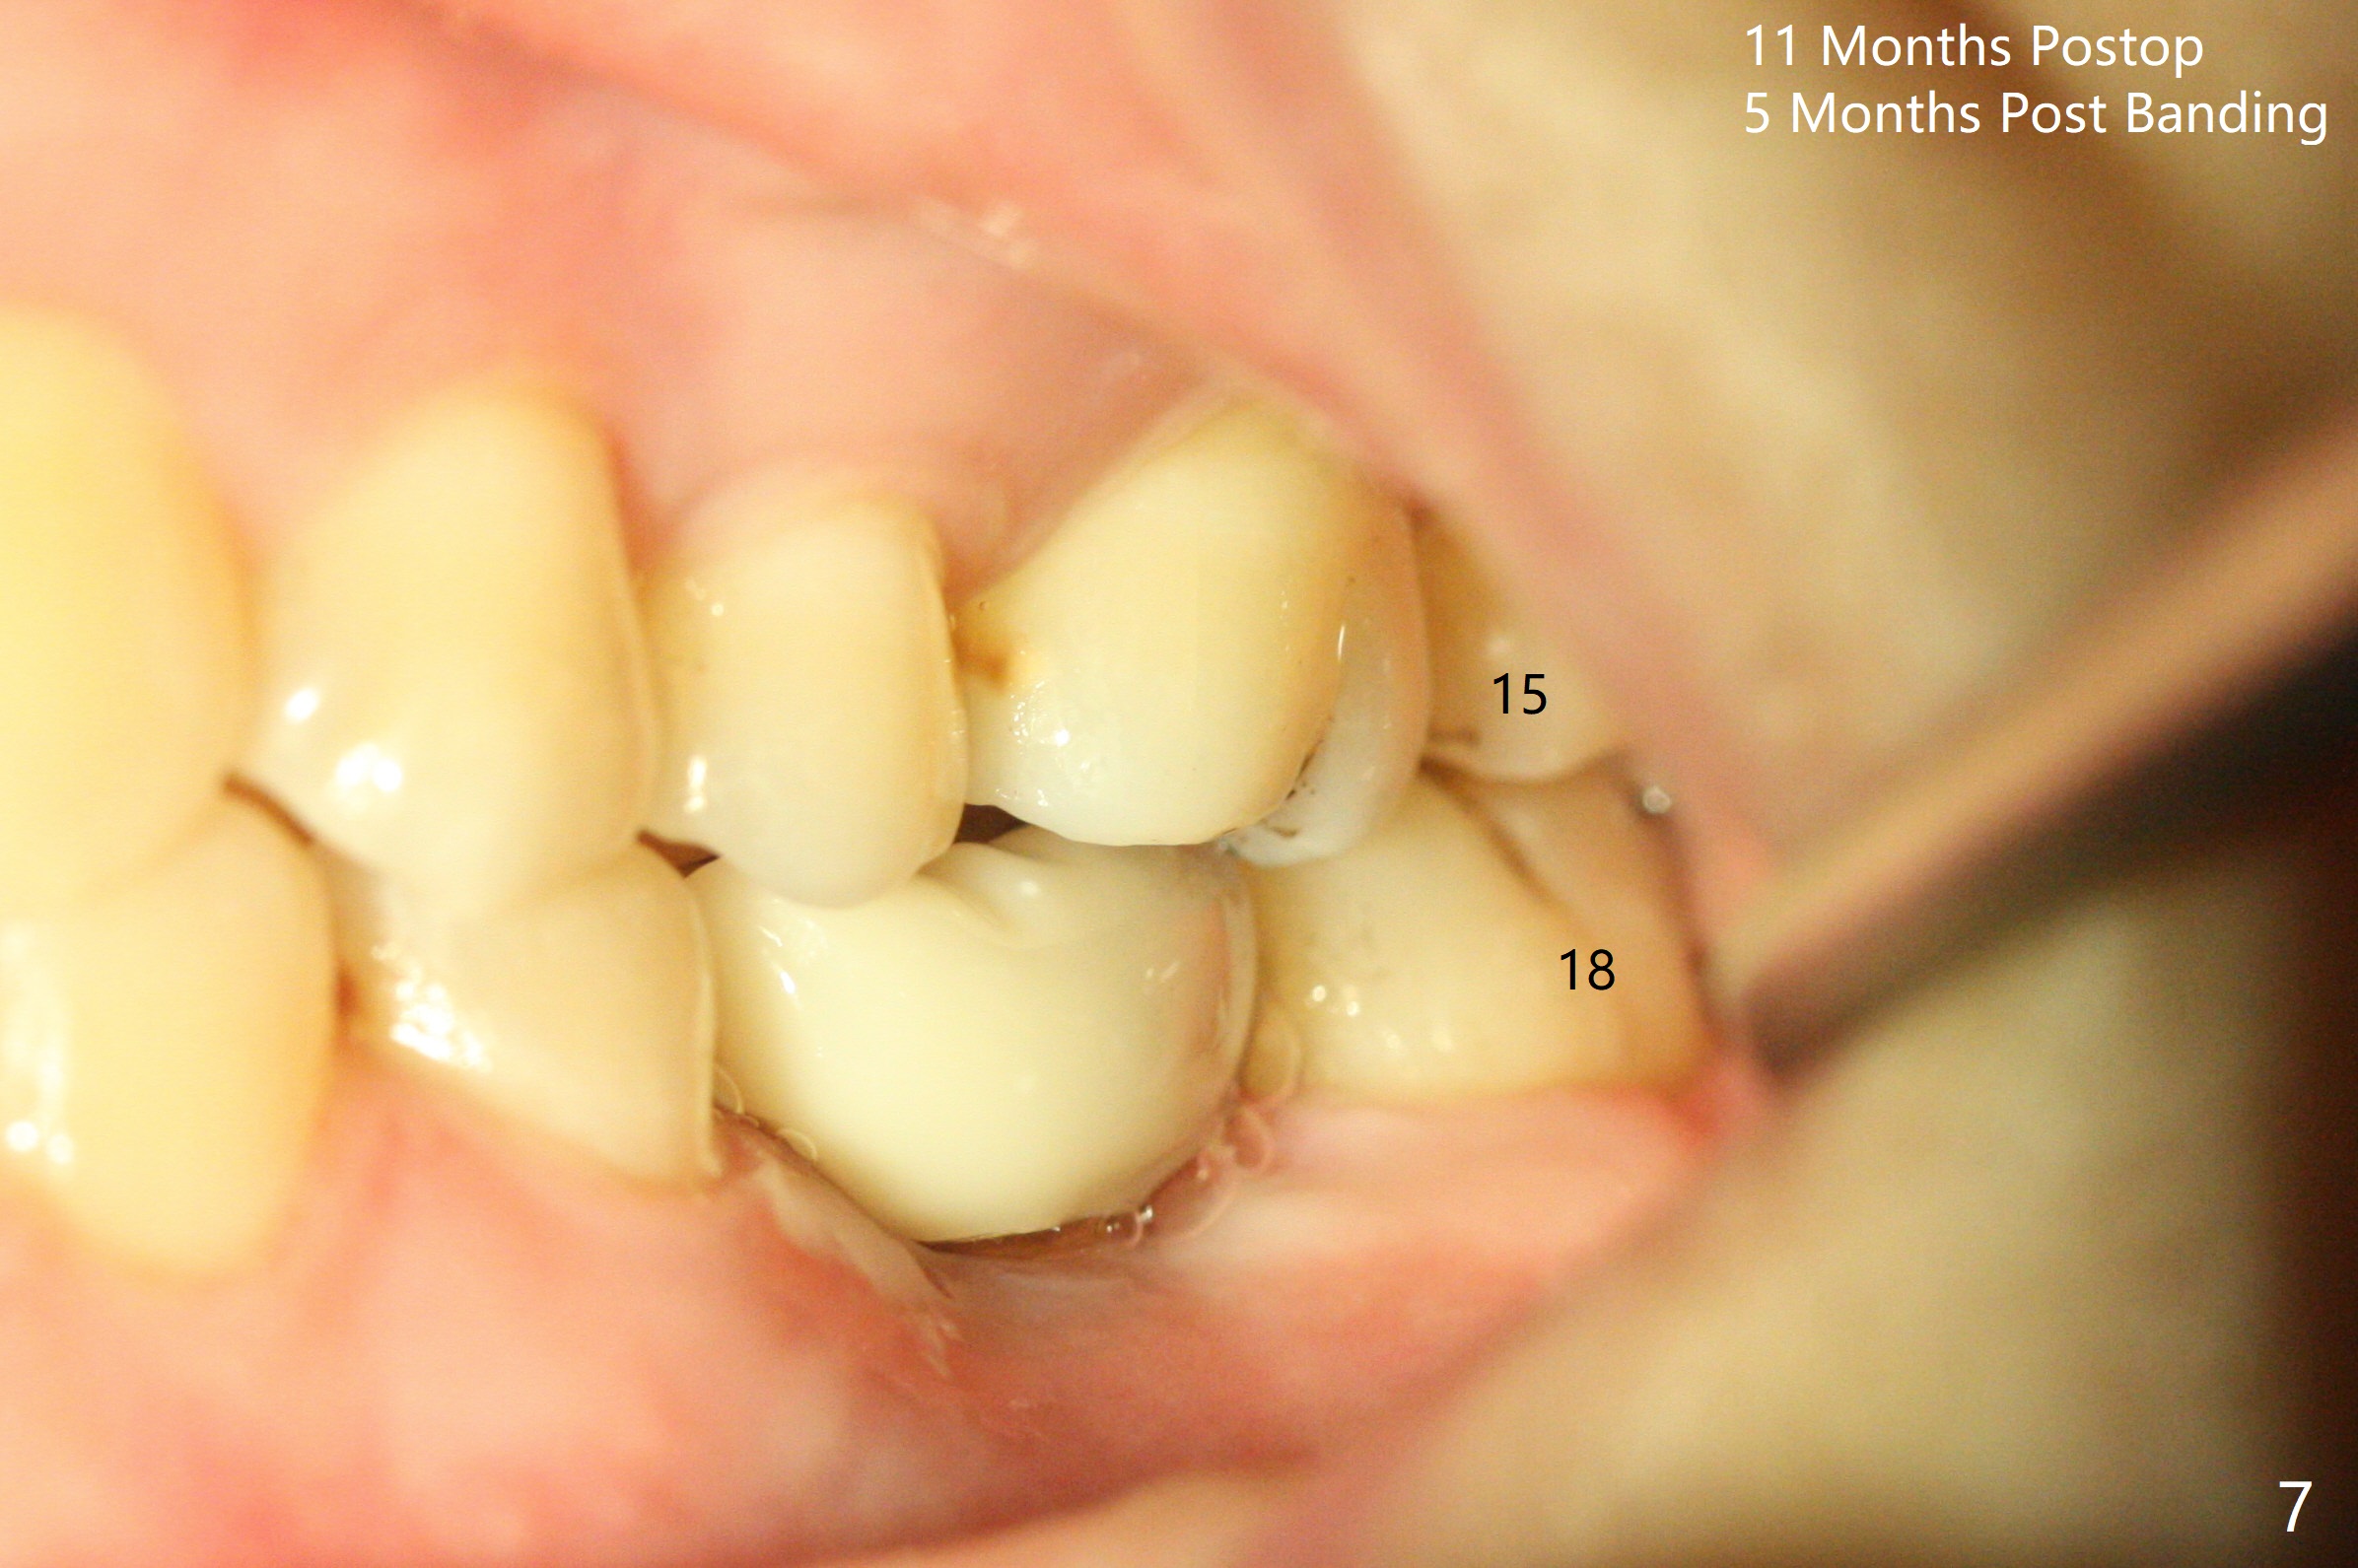

A 5x10 mm implant is intentionally placed distal at #19 using guided surgery (Fig.1). When it is osteointegrated, it will be used as an anchorage to upright the tooth #18 orthodontically. In fact the implant is mistakenly placed 1.5 mm deeper than planned without significant side effect (red dashed line: the superior border of the Inferior Alveolar Canal). The tooth #17 will be extracted before banding. The healing abutment dislodges (probably as related to deep placement of the implant) 20 days postop and is retightened. There is mild crestal bone loss 4 months postop (Fig.2). The tooth #17 is extracted with insertion of Osteogen Plug to prevent dry socket. A 5x4(2) mm cementation abutment will be placed with fabrication of a provisional with equi- or slightly subocclusal. Bands and brackets will be placed at #18-22. When open coil spring is placed between #18 and 19 with 18 ss wire, acrylic will be added to the occlusal surface of the provisional so that the tooth #18 is distalized without interference. The tooth #18 is distalized more than 1 month post placement of open coil spring (Fig.3). The tooth #18 is also lingually tilted (Fig.5), as compared to the contralateral side (Fig.4). After placement of 20 ss wire and longer coil spring, an elastic is placed between the lingual cleat of #18 and the buccal (lingual) button of #15 (Fig.5) to correct the lingual tilt. The tooth #18 is distalized ~ 1 mm shown by X-ray, although more clinically, 2.5 months post open coil spring (Fig.6). The bone density around the implant, particularly mesial, increases, as compared to Fig.2. The treatment finishes with normal overjet in the 2nd molars 11 months postop and 5 months post banding (Fig.7). It appears that the buccal groove of the lower 2nd molar (Fig.8 >) has been distalized to occlude with the mesiobuccal cusp of the upper 2nd molar (^). The width of the dense bone around the implant increases 14 months postop (3 months post cementation, Fig.9).